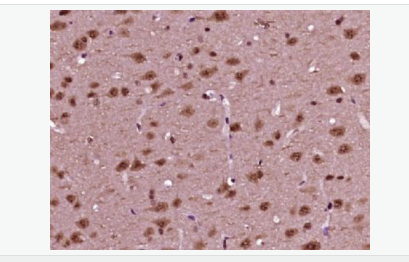

磷酸化神經細胞分化因子1抗體

Rabbit anti-phospho-NeuroD1 (Ser274) Polyclonal antibody

英文名稱phospho-NeuroD1 (Ser274)

中文名稱磷酸化神經細胞分化因子1抗體

別    名NeuroD1 (phospho S274); p-NeuroD1 (phospho S274); atonal; basic helix loop helix transcription factor; BETA 2; Beta cell E box transactivator 2; BETA2; BHF 1; BHF1; bHLHa3; class A basic helix loop helix protein 3; Class A basic helix-loop-helix protein 3; MODY 6; MODY6; NDF1_HUMAN; NEUROD; NeuroD1; Neurogenic differentiation 1; Neurogenic differentiation factor 1; neurogenic helix loop helix protein NEUROD; NIDDM.

產品類型磷酸化抗體

研究領域腫瘤  心血管  細胞生物  神經生物學  表觀遺傳學

產品應用WB=1:500-2000 ELISA=1:5000-10000 IHC-P=1:100-500 IHC-F=1:100-500 ICC=1:100-500 IF=1:100-500 (石蠟切片需做抗原修復)

細胞定位細胞核 細胞漿

免 疫 原KLH conjugated Synthesised acetylpeptide derived from human NeuroD1 around the acetylation site of Ser274:PL(p-S)PP

產品介紹This gene encodes a member of the NeuroD family of basic helix-loop-helix (bHLH) transcription factors. The protein forms heterodimers with other bHLH proteins and activates transcription of genes that contain a specific DNA sequence known as the E-box. It regulates expression of the insulin gene, and mutations in this gene result in type II diabetes mellitus. [provided by RefSeq, Jul 2008]

Differentiation factor required for dendrite morphogenesis and maintenance in the cerebellar cortex. Transcriptional activator. Binds to the insulin gene E-box.

Phosphorylated. In islet cells, phosphorylated on Ser-274 upon glucose stimulation; which may be required for nuclear localization. In activated neurons, phosphorylated on Ser-335; which promotes dendritic growth.

Defects in NEUROD1 are the cause of maturity-onset diabetes of the young type 6 (MODY6) [MIM:606394]. MODY is a form of diabetes that is characterized by an autosomal dominant mode of inheritance, onset in childhood or early adulthood (usually before 25 years of age), a primary defect in insulin secretion and frequent insulin-independence at the beginning of the disease.